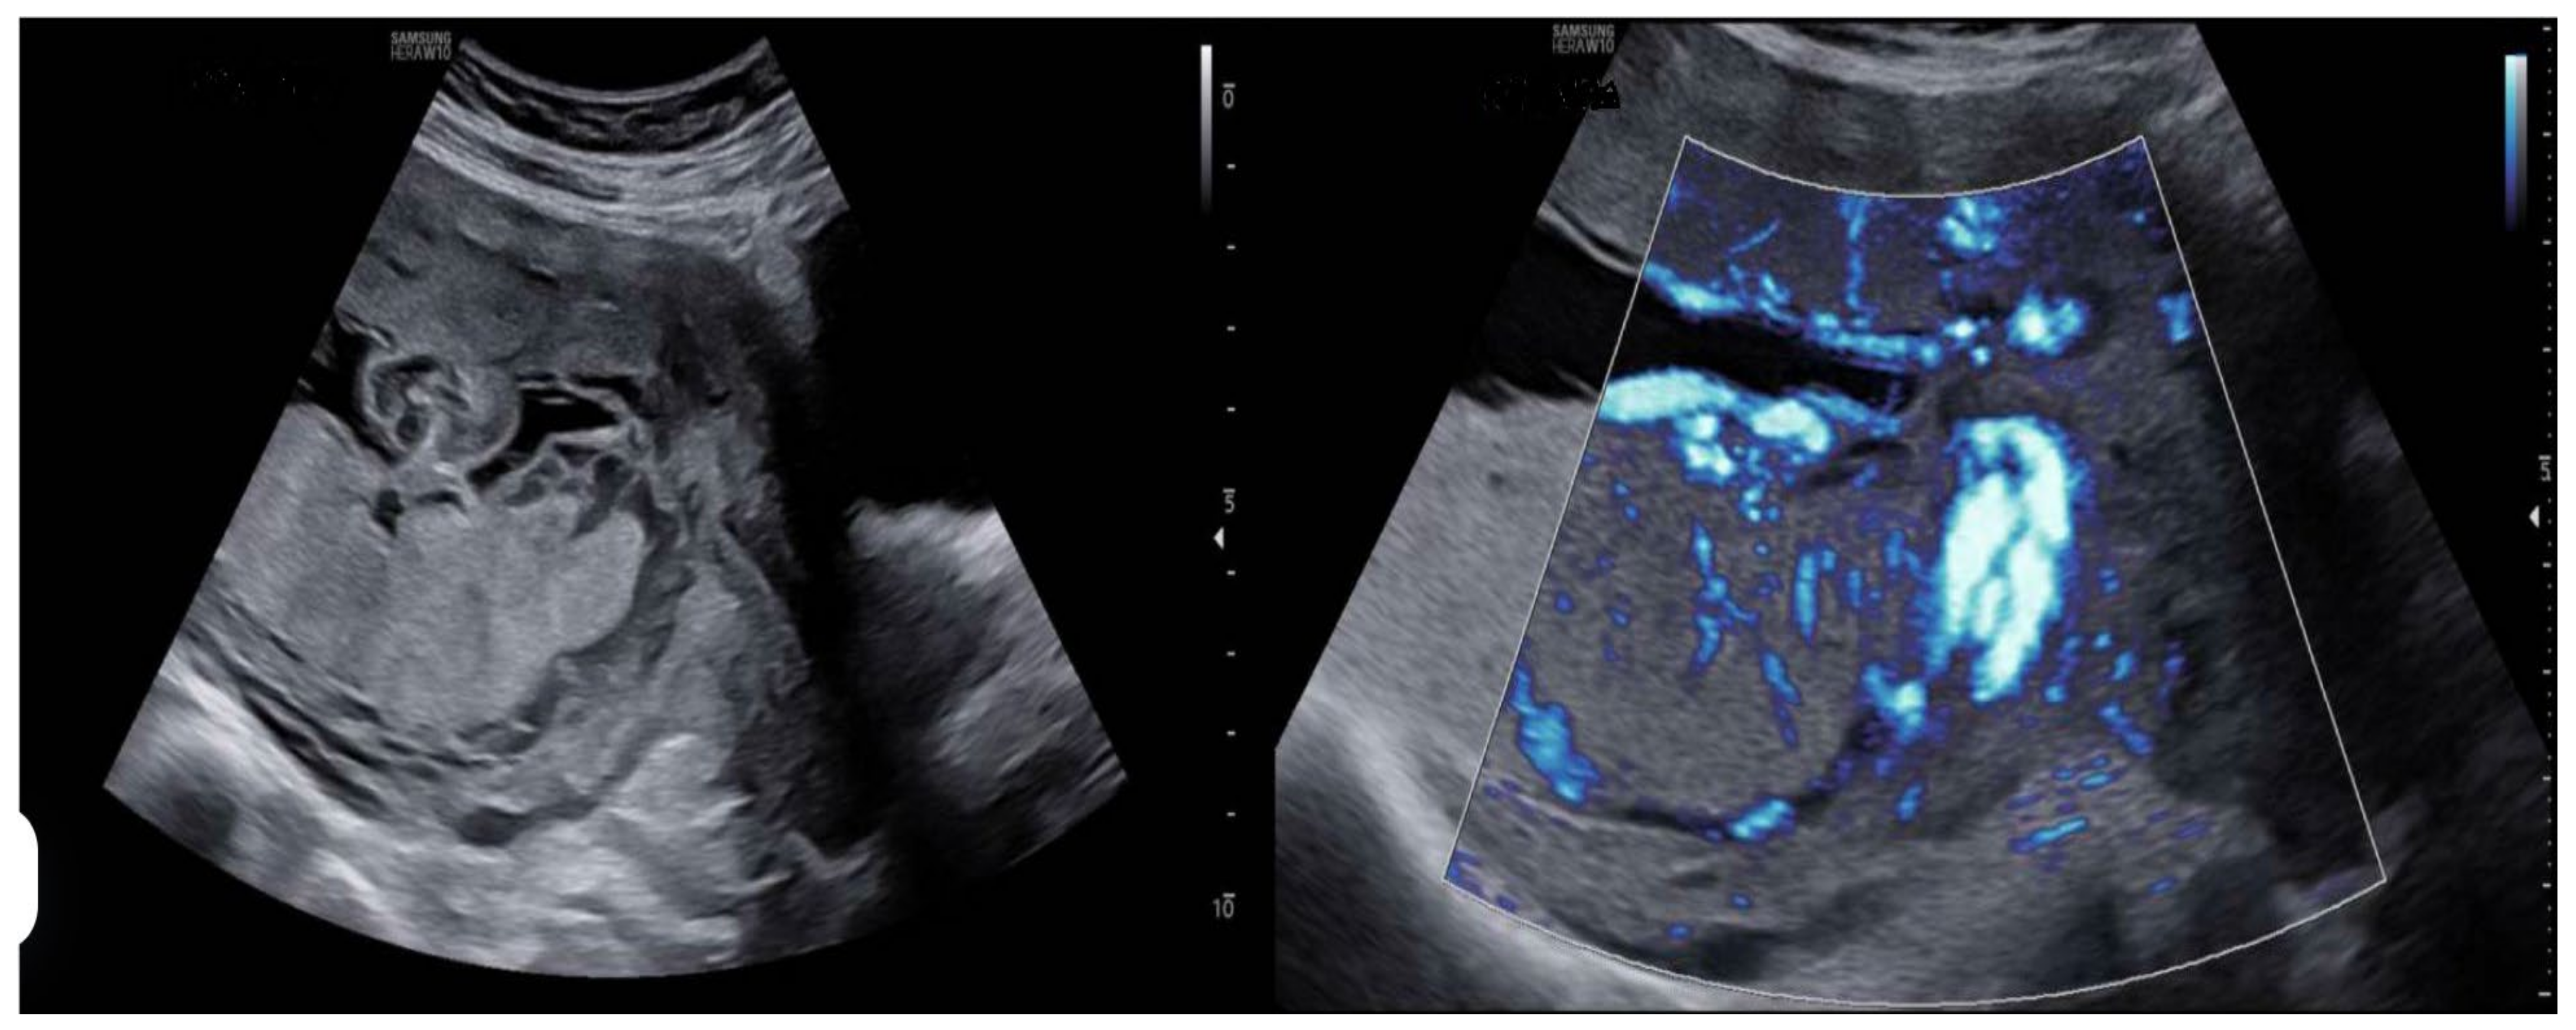

- Prenatal ultrasound evaluation: morphological description of the main placenta and accessory lobe, precise determination of umbilical cord insertion site, color Doppler assessment of vascular connections between lobes, and transvaginal ultrasound to rule out vasa previa.

- Color Doppler assessment to identify vascular connections between lobes.